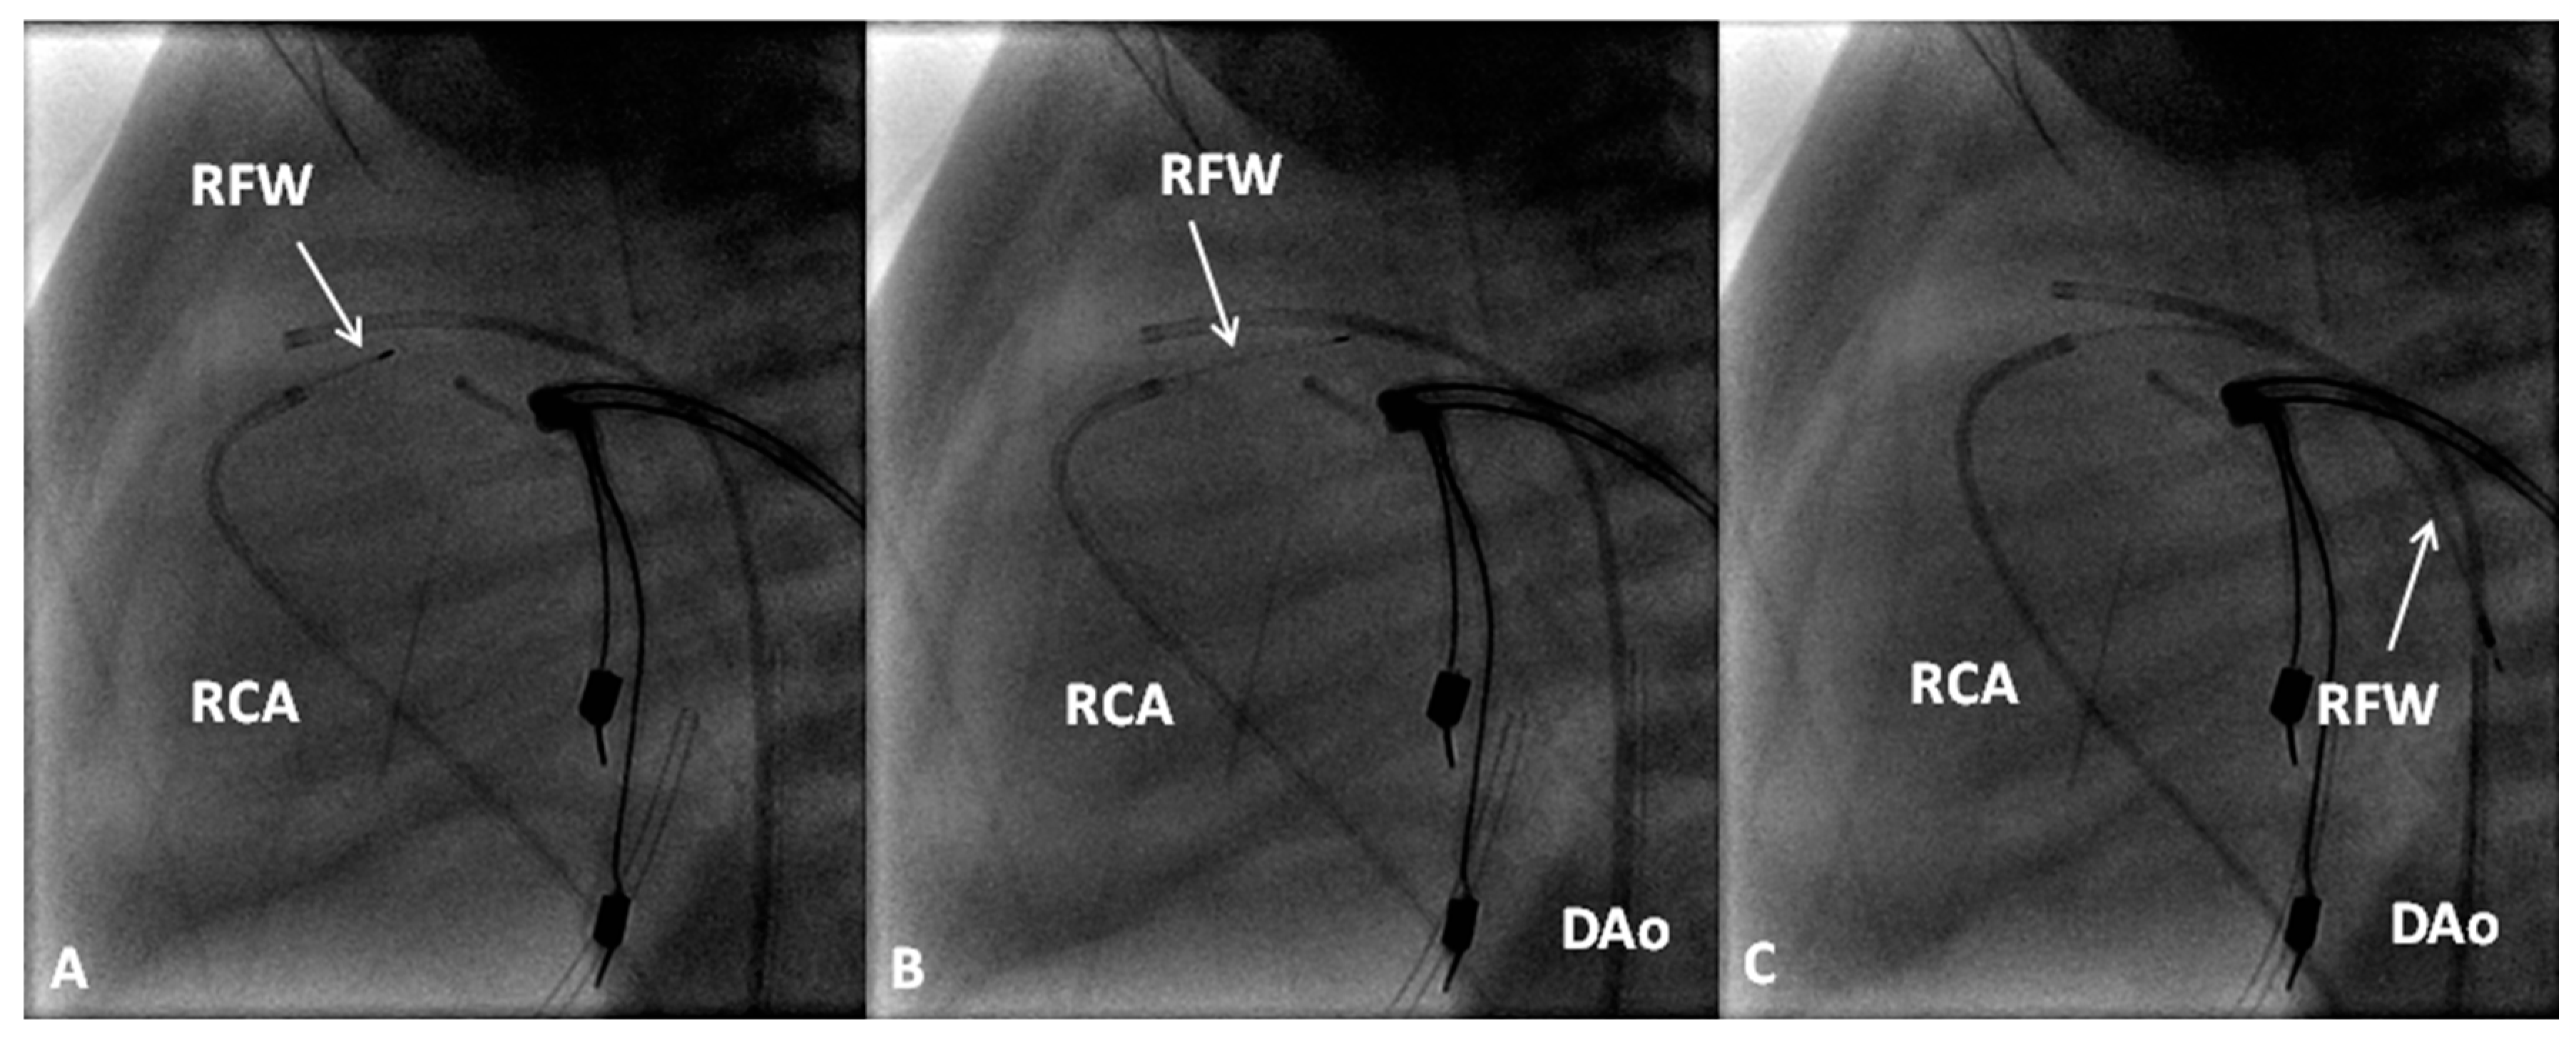

If the RV is of reasonable size and tripartite or bipartite in nature (Figure 14), trans-catheter perforation with radiofrequency wire (Figure 15) followed by balloon valvuloplasty is performed to restore RV to PA continuity (Figure 16 and Figure 17).